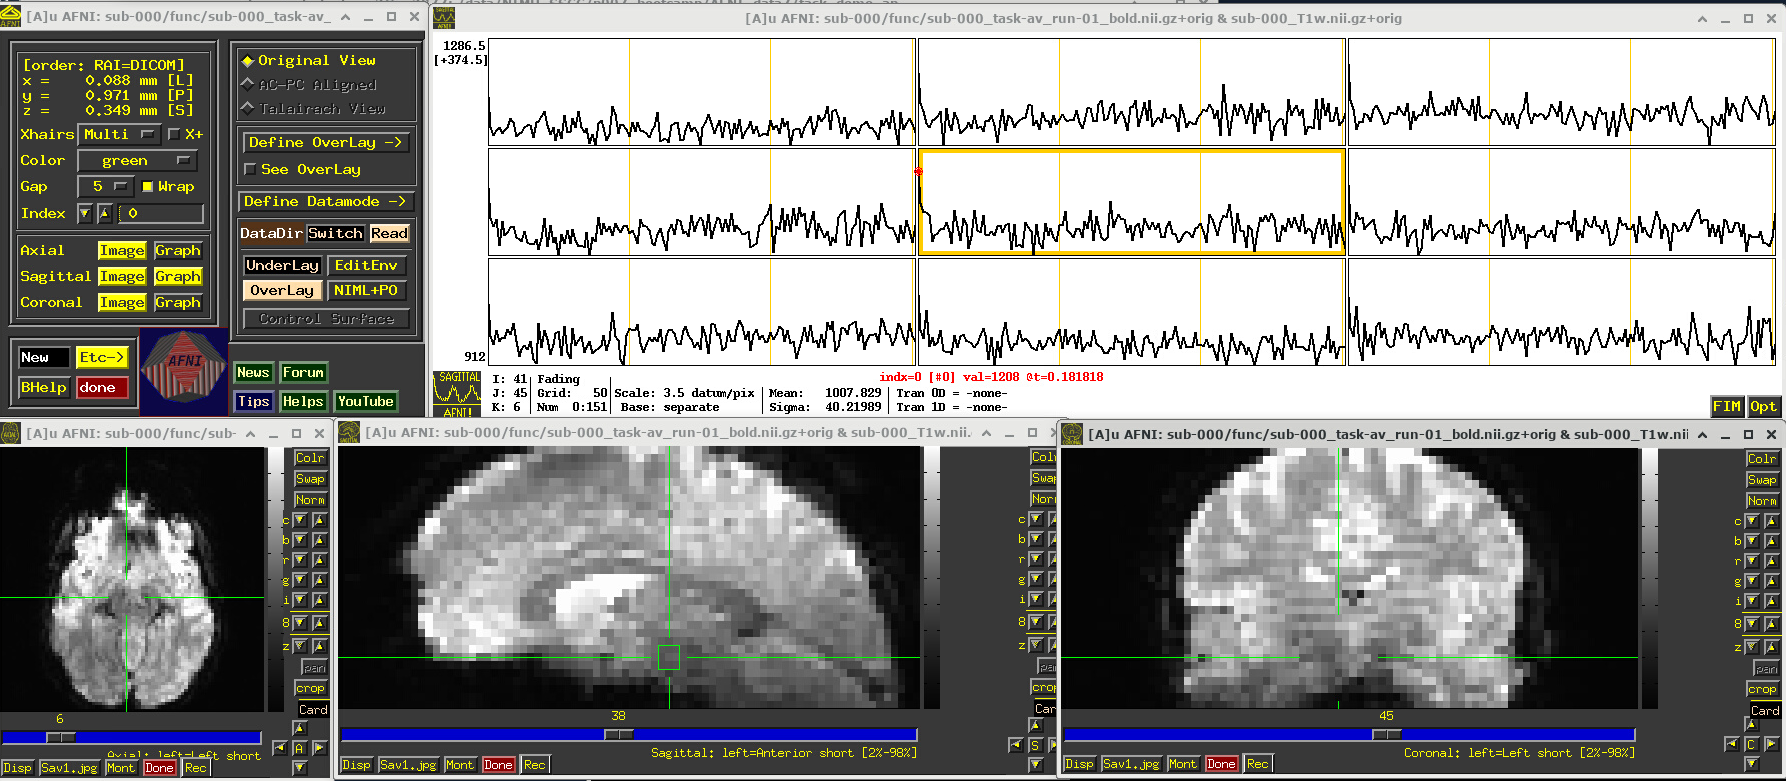

# Display a screenshot of the AFNI GUI with the first EPI run loaded

IPython.display.Image(filename='example_snapshots/img_03_afnigui_epi_r01_taskresp.png')

../../_images/df242a56362284883d4e5b72322ff8de8574fb812b73727711a90463314798b7.png

The task performed during this FMRI scan was an audio-visual one. So, let’s check out how things look in the visual cortex. Well, see see some notable patterns, such as at the location (x,y,z) ~ (16, 78, 3.3), as below. While the earlier-noted motion and pre-steady state spikes apparent, we now see some very regular pattern of hills. And indeed, these are signatures of task-related BOLD response for this block design paradigm (we could load the idealized response time series into the graph viewer, too, to help verify this).

Specifically, this paradigm has the start of a block that contains either a blurred or clear visual component every 30s and a duration of 20s, so seeing regular response in the visual cortex is not unexpected. The fact that we see a few time series in this graph montage with the task signature reflects our spatial sampling: the voxel edges are roughly the same diameter as GM cortex. Notice also that the response shapes aren’t perfectly rectangular—the BOLD response is not on/off, but has a ramp up and ramp down—and that notable plus/minus noise bumps are still present.

Later, we will look at performing real processing to get a more detailed description of task responses: quantifying each stimulus class, perhaps comparing them (i.e., evaluating their “contrast”), trying to boost their signal-to-noise ratio while also reducing spikes and other noise features. That is the job of the real processing.